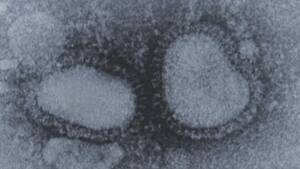

毎年流行し、死亡者も少なくないインフルエンザ。予防策の一つとして、昨年から新たに経鼻弱毒生インフルエンザワクチン(通称・フルミスト)の接種が始まった。

注射器を使わず、鼻に噴霧するため、痛みを感じずにワクチンを接種することが可能。一方、生きた弱いウイルスが成分となっているため、副反応として鼻づまりや鼻水などの症状が接種者の半数以上で確認され、飛沫や接触によるワクチンウイルスの水平伝播の可能性もあるという。日本小児科学会は喘息患者や妊婦、授乳婦などへの接種は推奨していない。

フルミストは2003年に初めて米国で、国内では23年に製造販売が承認された。厚労省によると、これまで使用されてきた海外での有効性は成人では従来の筋注製剤に対する優越性が示されておらず、50歳以上は効果も示されていない。そのため日本では適応年齢は2〜19歳未満となっており、市内でも小児科を中心に取り扱われている。